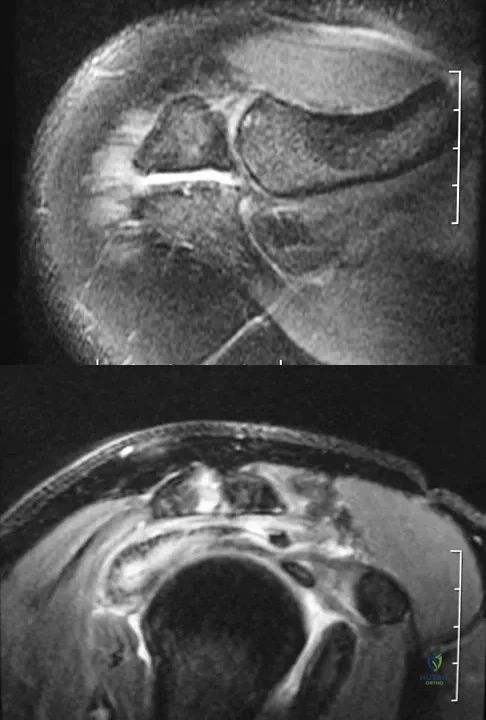

Figures 34a and 34b show the axial and sagittal MRI scans of a 36-year-old man who reports the insidious onset of pain in the right shoulder. What is the most appropriate description of the acromial morphology?